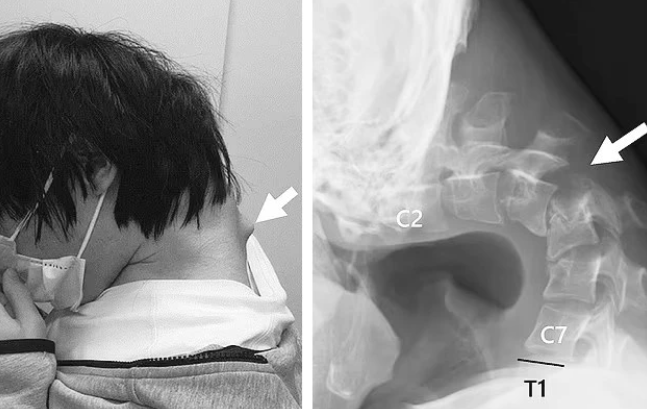

Mới nhất, một nam thanh niên 25 tuổi bị vẹo vọ cổ sau thời gian dài sử dụng điện thoại để chơi game. Cổ của bệnh nhân yếu đến mức không thể tự nâng đầu lên. Phim chụp cho thấy phần cổ của anh biến dạng với khối phồng rõ rệt, do các đốt sống bị kéo giãn bất thường trong thời gian dài. Được biết, bệnh nhân đã chịu đựng cơn đau cổ nghiêm trọng suốt 6 tháng trước khi tìm đến bệnh viện. Anh cũng gặp khó khăn khi nuốt dẫn đến ăn ít và sụt cân nghiêm trọng.

Trường hợp này được công bố trên JOS Case Reports với sự đồng ý của bệnh nhân và gia đình.

Các chuyên gia cho rằng tình trạng trên có thể do sự kết hợp giữa việc giữ tư thế cổ sai lệch trong thời gian dài và một rối loạn phát triển tiềm ẩn. Họ kêu gọi nâng cao nhận thức về tác hại của việc lạm dụng điện thoại thông minh, đặc biệt ở giới trẻ.